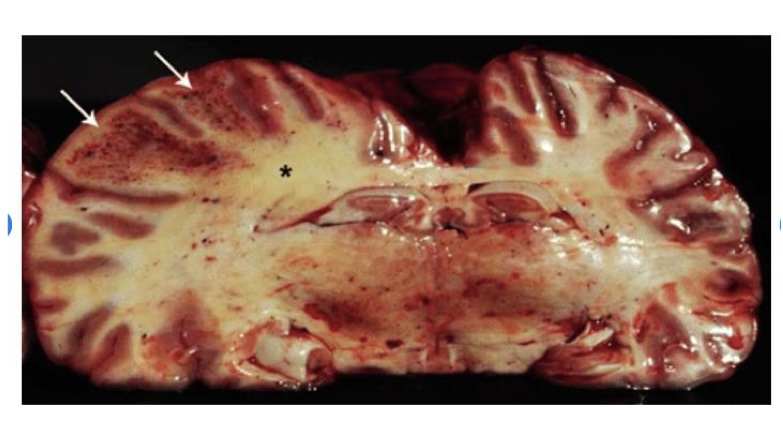

what is this?

astrocytoma

right hemisphere contains a poorly demarcated, nonencapsulated, expansile mass

lesion has displaced the midline to the left and compressed the right lateral ventricle